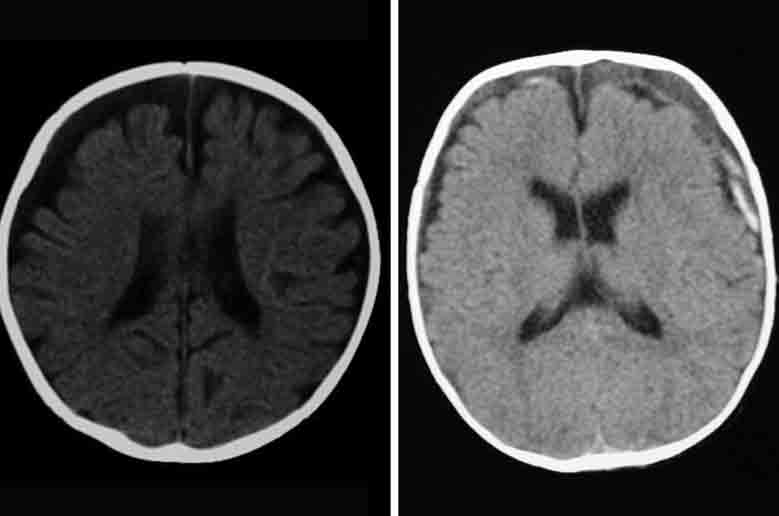

Définition de hématome : dictionnaires de référence, étymologie, phonétique, citations littéraires, synonymes et antonymes de Hématome : définition du Trésor de la Langue Française informatisé. L'hématome sous-dural désigne une collection sanguine se trouvant dans l'espace sous-dural, espace qui est délimité par l'arachnoïde et le feuillet interne de la dure-mère. Il résulte d'un traumatisme, d'une rupture vasculaire ou d'un trouble de la crase sanguine.